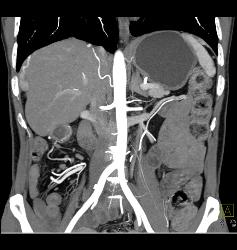

Diagnosis

Hamartoma